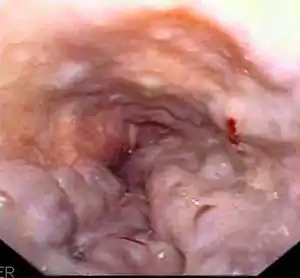

Esophageal varices are extremely dilated sub-mucosal veins in the lower third of the esophagus.[1] They are most often a consequence of portal hypertension,[2] commonly due to cirrhosis.[3] People with esophageal varices have a strong tendency to develop severe bleeding which left untreated can be fatal. Esophageal varices are typically diagnosed through an esophagogastroduodenoscopy.[4]

| Gastroscopy image of esophageal varices with prominent cherry-red spots and wale signs | |

Dilated submucosal veins are the most prominent histologic feature of esophageal varices. The expansion of the submucosa leads to elevation of the mucosa above the surrounding tissue, which is apparent during endoscopy and is a key diagnostic feature. Evidence of recent variceal hemorrhage includes necrosis and ulceration of the mucosa. Evidence of past variceal hemorrhage includes inflammation and venous thrombosis.